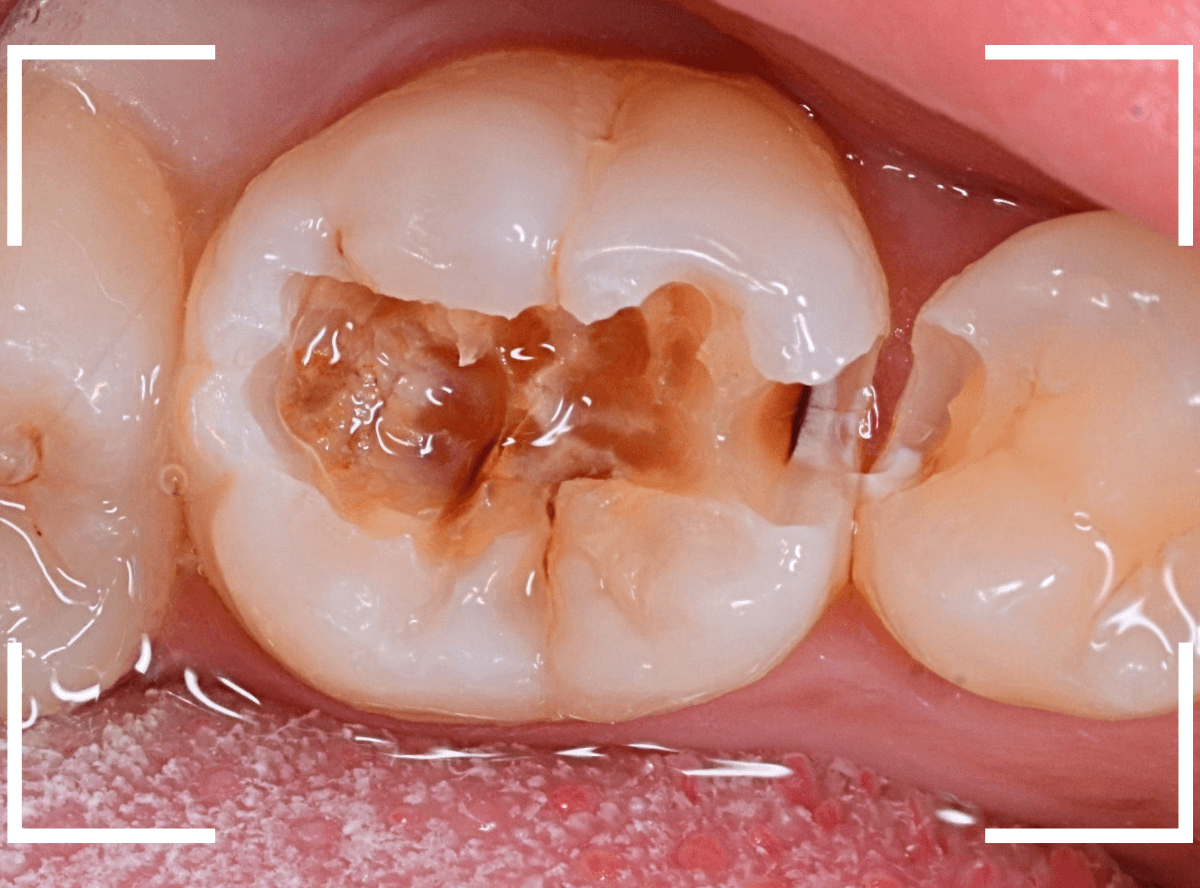

Case.3 歯の表面の小さな溝から広がった、虫歯の治療 <動画編>

今回は、かなり内部で虫歯が広がっていた、小窩裂溝う蝕の治療例です。

歯を上から確認すると、溝の周りが虫歯がありそうです。

レントゲン写真で確認すると、やはり、中で虫歯が進行していました。

このように、入り口が狭くても、中で広がっている虫歯はとても多いです。

虫歯は色々な所から静かに深く進行しています。

症状がなくても、定期検診に通う事で虫歯のリスクは大きく下げる事が出来ますよ。